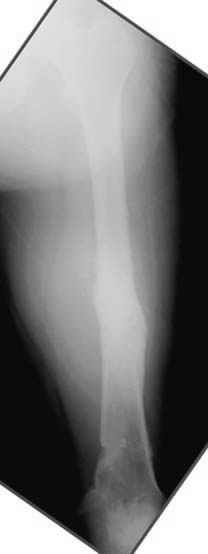

Несколько снимков из моей коллекции, чтобы разьяснить, почему мы до сих пор делаем различные варианты остеотомии.

На рисунке N1 предоперационный план лечения ложного сустава шейки бедра- линия ложного сустава, угол и направление введения импланта, клиновидная остеотомия в градусах и миллиметрах, второй снимок после коррекции, расчет, на сколько удлиняется конечность и размеры импланта;

N3 рисунок окончательный снимок, после операции моя рентгенограмма должен выглядеть примерно как эта картина. На N4 снимке клин перед удалением; N5 послеоперации 3 нед.; N6 окончательная рентгенограмма.

Отправитель: Djoldas Kuldjanov 23 Ноябрь 2004, 18:21

пластическая модель; и коррекция бедра аппаратом Илизарова.

Узкий к-м канал - тонкий гвоздь- усталостный перелом дистальных винтов - развитие нестабильности и как ее результат остеолиз вокруг гвоздя - деформация анатомической оси бедра. Похоже, что я понял почему аппарат, а не новый гвоздь:-)